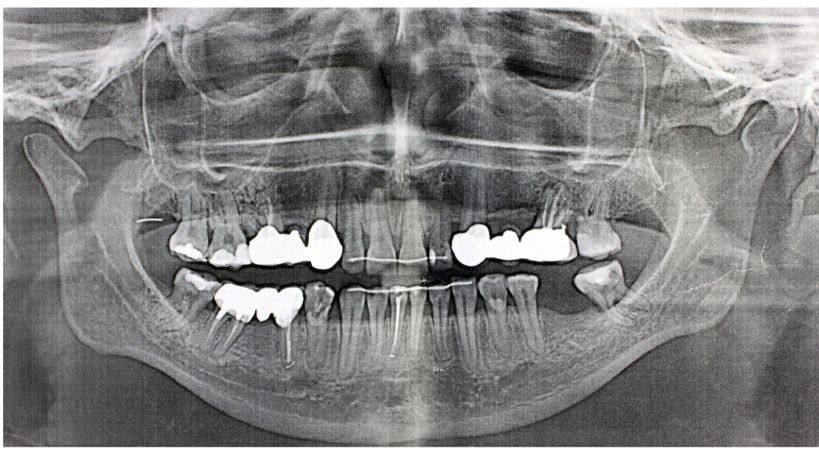

La técnica Socket-Shield

Planificación digital, cirugía guiada y carga inmediata de implantes: seguimiento de 2 años